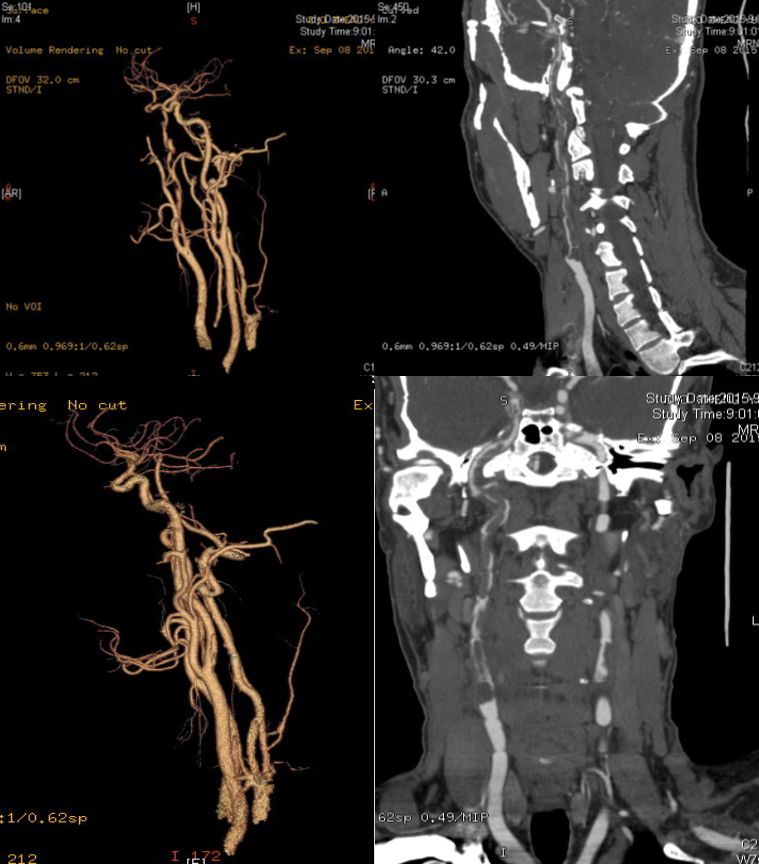

男性35岁。因头晕、左侧肢体无力半天入院。既往:发现血压偏高7-8年;嗜烟酒。查体:血压120/80mmHg,左侧偏瘫。实验室检查:红细胞 5.62*1012/L,Hb185g/L,抗磷脂抗体阴性。

答案:颈内动脉巨大漂浮血栓。颈动脉自由漂浮血栓(附着于血管壁的瘦长血栓,其远端大部仍有栓周血流)罕见,文献报道不超过150例。最常见的病因为动脉粥样硬化或溃疡斑块,也见于高凝状态、高纤维蛋白原血症、缺铁性贫血、血小板增多症、兴奋剂使用者。治疗以抗凝和稳定斑块为主。不常规考虑血管内治疗。因为:1)该血栓为延伸性,而非堵塞性;2)患者神经功能缺损相对轻;3)由于再发栓塞的风险很高,应当避免针对血栓的机械操作。若患者的临床症状恶化,应当进行紧急的机械取栓治疗(如抽吸血栓)。病情稳定后可行颈动脉内膜剥脱术。